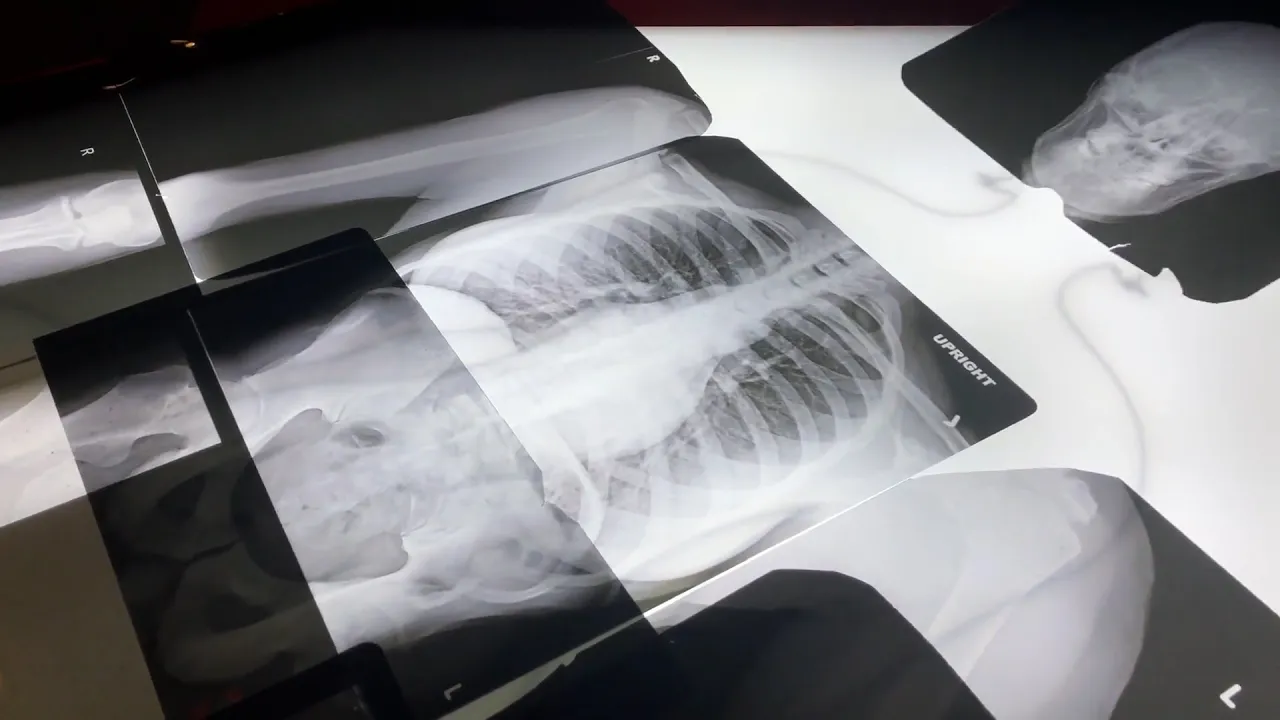

En 1895, Wilhelm Conrad Röntgen, experimentó con un tubo de rayos catódicos en Alemania, es decir, los conocidos rayos X. En ese momento, le pidió a su mujer que colocara su mano sobre una placa de metal para “fotografiarla”. De esta manera, se obtenía la primera radiografía de la historia. En los inicios, los rayos X eran “una atracción de feria”. Sin saber los peligros que conllevaba, la gente hacía cola para descubrir qué había en el interior de su cuerpo, hasta que se tomó conciencia de lo perjudicial que era y se dejó de hacer. Finalmente, los rayos X se empezaron a usar en medicina en 1896.